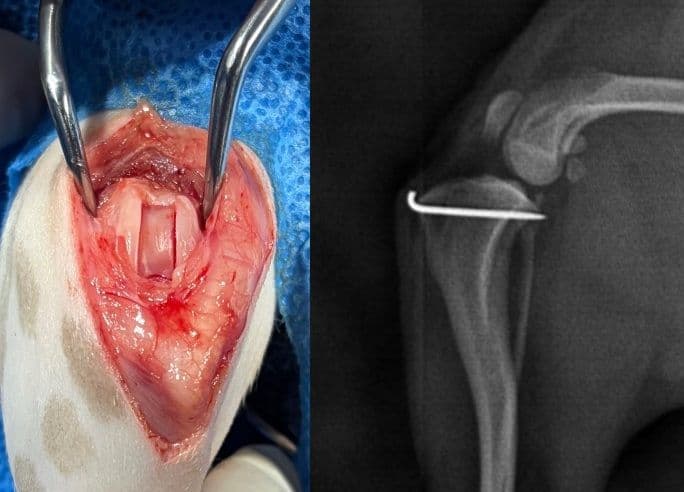

십자인대 수술

TPLO, CBLO, CTWO, 낭외고정술

슬개골 탈구 교정술

TTT, DFO, PTO